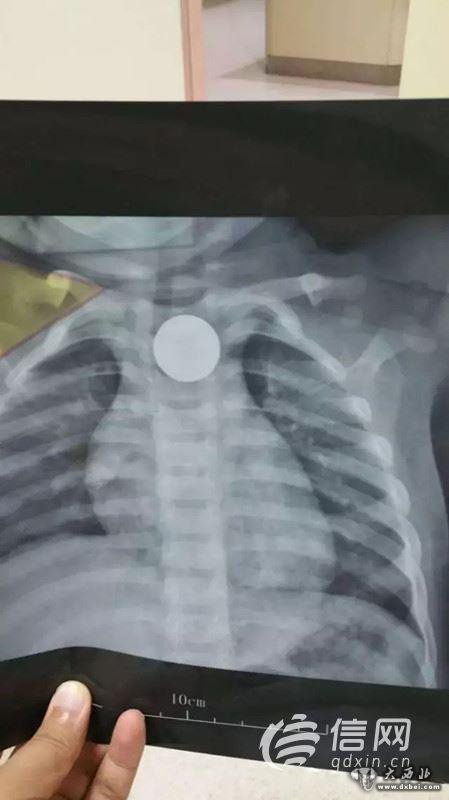

7月12日晚10:20,一名家长抱着一个14个月大的孩子急匆匆走进青岛市妇女儿童医院耳鼻喉科急诊值班室。“5个小时前孩子误吞下了一枚遥控器的直径为2.2cm的纽扣电池,我们当地医院确诊为电池卡入食道。”

晚上11点10分,患儿被送入手术室,麻醉师和护理人员一边安抚患儿,一边进行麻醉处置和各项护理操作,整个手术间弥漫着紧张的气氛。“因为患儿年龄太小,最小号的食道镜在进入食道时也遇到了很大的阻力,2.2厘米大的异物只能和食道镜一起撤出。”经过手术医生的反复努力,发现电池卡在食道入口下方约2厘米处,电池被顺利取出,此时在场的医护人员松了一口气。

“虽然电池被顺利取出,但是此时的电池表面已经发黑,局部食道黏膜已经红肿糜烂,且有黑色异物残留,手术医生用蒸馏水反复冲洗半个多小时才将残留的异物冲洗干净,患儿术后还需进一步治疗,是否出现严重并发症还需观察。”